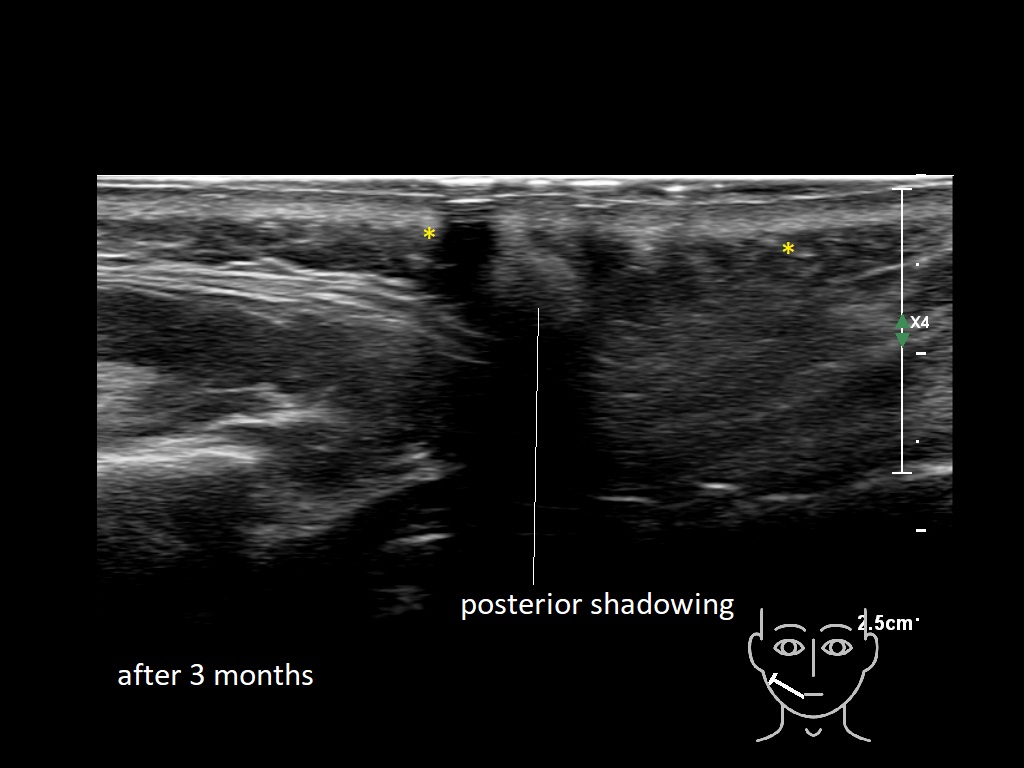

Draw in the second image below where the fillers are located. To check if your answer is correct, swipe the first image to the right.